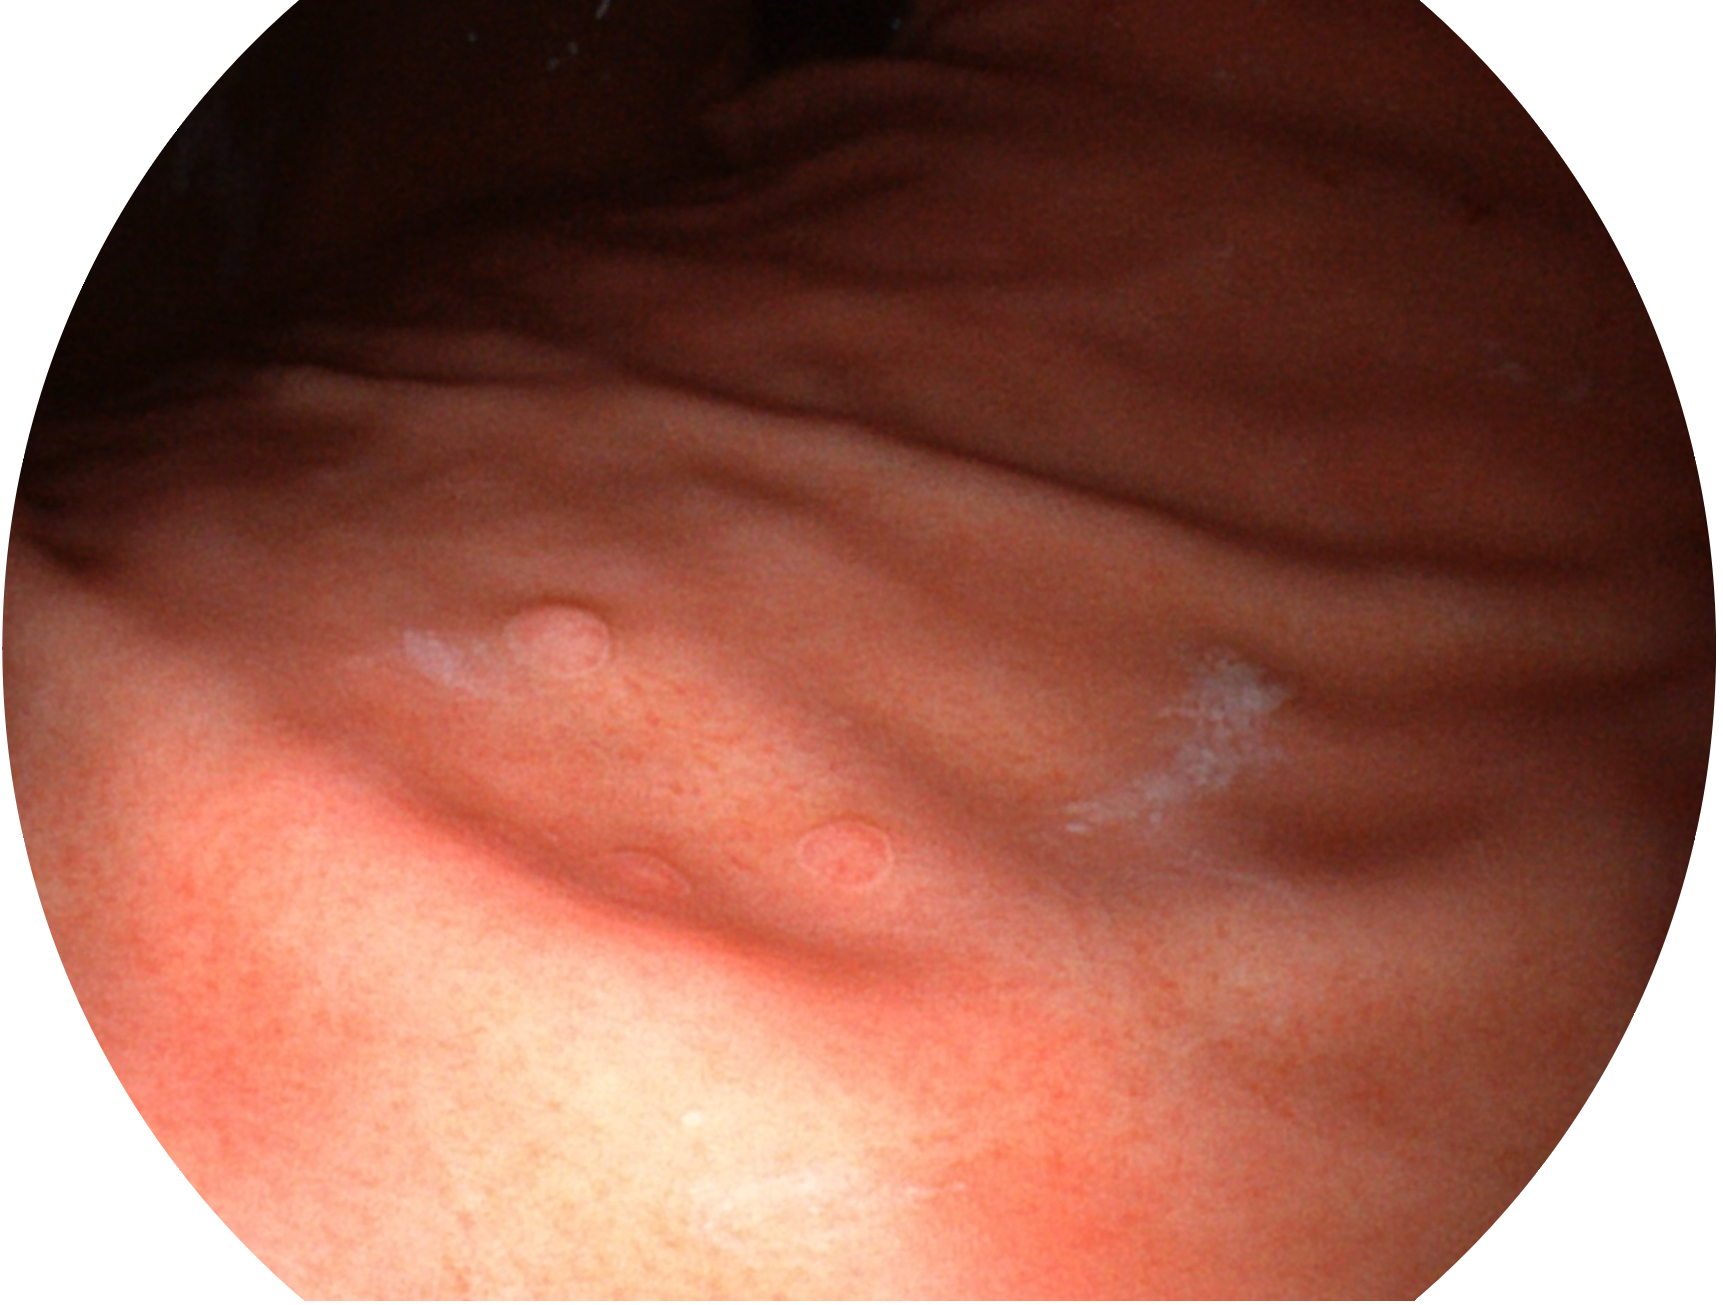

• 白光图像 SFI图像